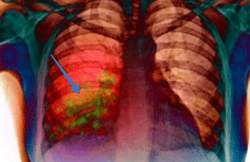

Клебсиелла пневмонии, или заболевание, вызванное этой бактерией, является довольно редким и обнаруживается только у 4% больных. Этот вид воспаления легких характеризуется образованием большого количества очагов, которые быстро объединяются и распространяются на большие участки тканей.

Чаще всего пневмония, вызванная клебсиеллой, приводит к развитию плеврита, фибринозного или экссудативного характера. Кроме того, этот микроорганизм способствует блокировке сосудов в легких, что может привести к развитию инфаркта.

Клебсиелла представляет особую опасность для ткани альвеол. Поражение этой бактерией может вызвать развитие гнойных процессов, которые могут привести к некрозу тканей. Патологические изменения в альвеолах при клебсиеллезе часто приводят к частичной или полной ателектазии легких.